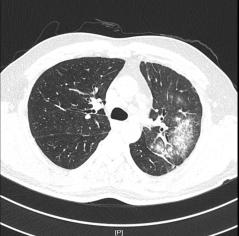

2020年5月14日行胸部CT:

1.左肺上叶炎症;

2.右肺上叶尖段慢性炎症;

3.两肺上叶、左肺下叶局限性肺气肿;

2020年5月24日复查胸部CT:

左肺上叶炎症,较前进展;

右肺上叶间质性病变,考虑间质性肺水肿;

右肺上叶尖段慢性炎症。

▎肺部增强CT(图片如下)

2.右上肺尖段少许慢性炎症;

3.纵隔多发肿大淋巴结,拟反应性增生,建议随诊;

4.拟左上肺多发体-肺动脉分流形成;

5.支气管动脉重建示左侧支气管动脉稍增粗。

反复阅读肺部CT并与影像科同事联系,患者肺部CT提示间质水肿、左肺上静脉显示不清,结合患者存在射频消融史,需要考虑肺静脉狭窄引起的咯血。

其中肺静脉增强CT检查及血管三维重建诊断PSV效果明显,该例患者我院首先完善了肺部动脉增强CT,影像科医生在报告中未报左肺静脉异常,我们反复阅读片子发现左肺静脉异常,从而进一步行右心导管、左心导管、肺动脉造影术,以此明确诊断;而使用心脏彩超诊断PVS中需警惕因操作者主观因素导致的诊断遗漏,注意加强与辅助科室之间的提醒。